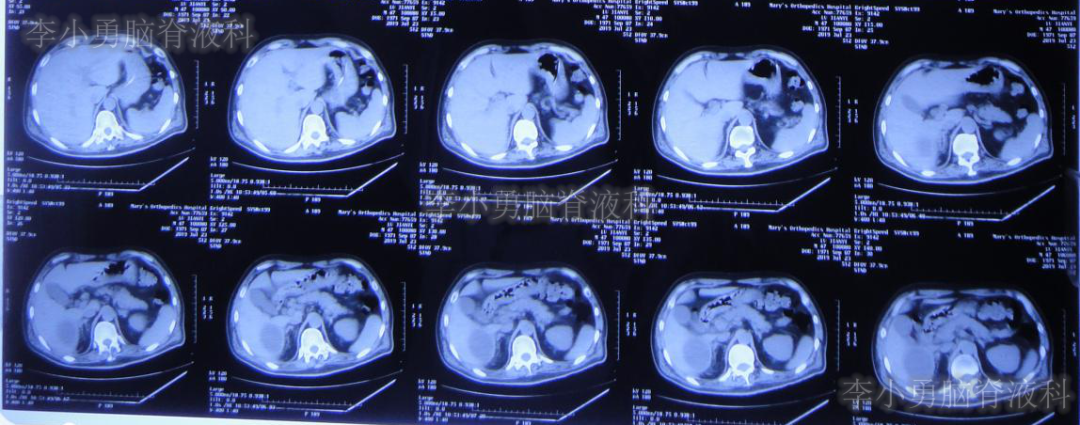

颅骨修补术+脑室腹腔分流术后105天即2019年7月12日(脑外伤术后194天),转至李小勇脑脊液科。入院时:患者呈昏迷状态,体温高,留置胃管、气管切开套管(图-9)。入院当天行头颅CT(图-10)示脑室扩张、腹部CT检查(图-11)可见肝区巨大的囊肿,其内可见引流管,考虑囊肿内为脑脊液。

图-11:2019年7月12日上腹部CT巨大的囊肿其内可见引流管

由于患者脑室明显扩大,且肝区巨大水囊(引流管包裹形成),考虑分流管已发生堵塞,故入院当天紧急行脑室外引流术+原分流管拔除术。术后次日复查头颅CT(图-12)示引流管位置良好,无出血。

脑室外引流术后第11天即2019年7月23日,复查腹部CT(图-14)显示肝区巨大水囊有明显缩小。

图-14:2019年7月23日腹部CT肝区水囊明显变小